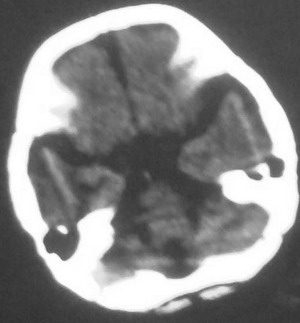

以下是引用dyqct在2008-7-30 17:05:00的发言:[br]考虑:1、胼胝体发育不全;[br] 2、肝豆状核变性(双侧豆状核对称性低密度)。

以下是引用同在2008-7-29 20:38:00的发言:[br]胼胝体发育不全.